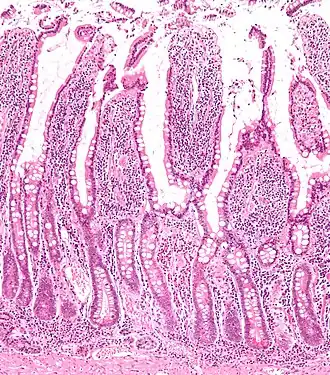

Micrograph of the small intestine mucosa showing the intestinal villi and crypts of Lieberkühn.

The three sections of the small intestine look similar to each other at a microscopic level, but there are some important differences. The parts of the intestine are as follows:

Mucosa: intestinal epithelium Simple columnar. Contains goblet cells, Paneth cells Similar to duodenum, but the intestinal villus is long Similar to duodenum, but the intestinal villus is short